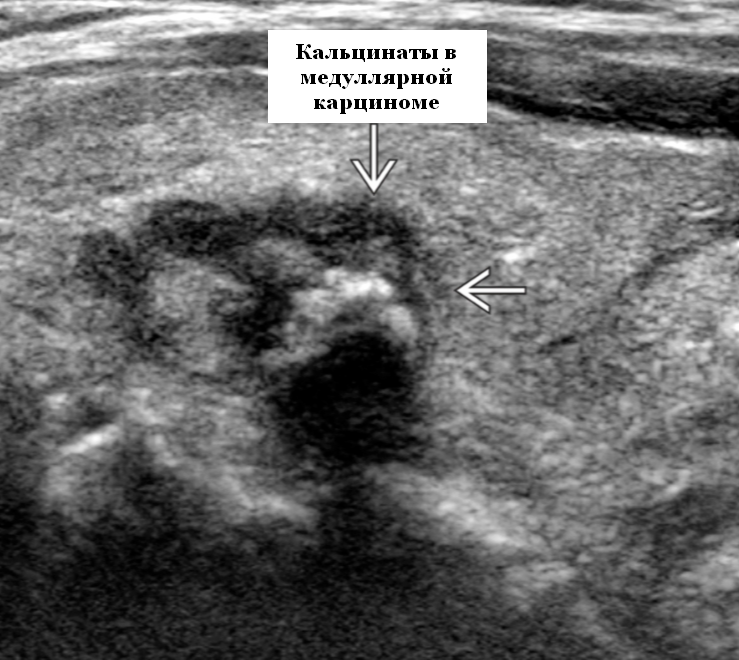

Фотографии опухоли медуллярной аденокарциномы

Раздел: Снимки-откровения